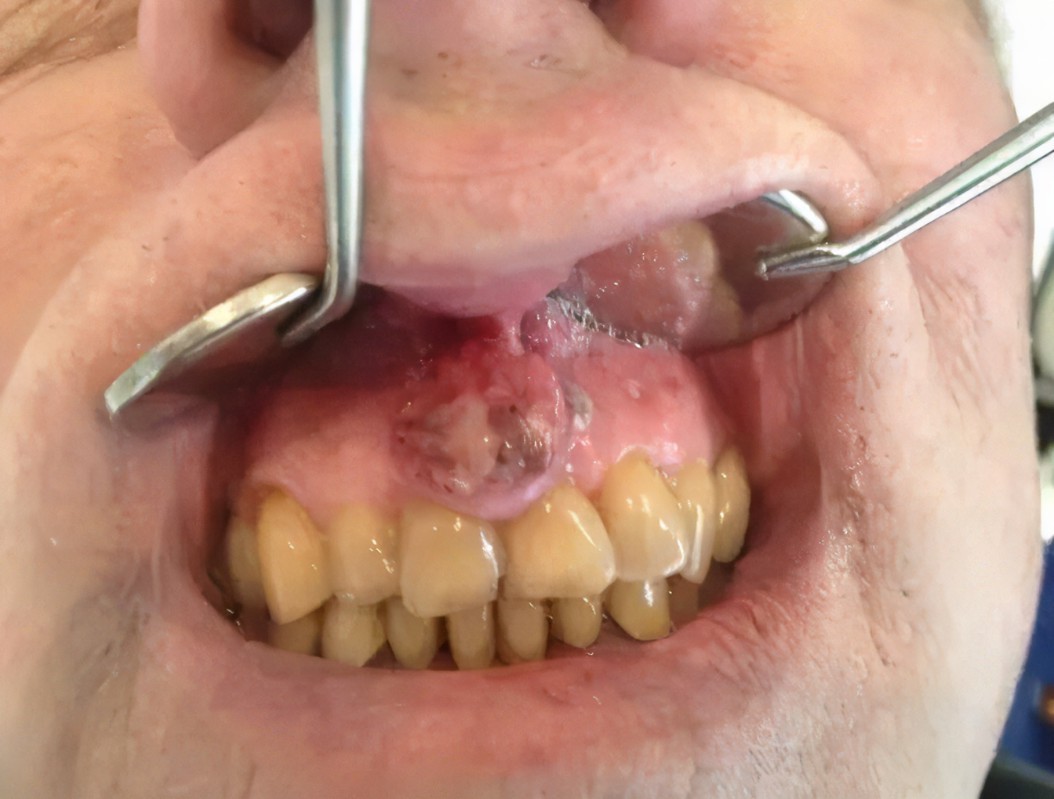

前几天我看了一个关于口腔癌的报道,真的是触目惊心,而导致这一幕的“凶手”就是-槟榔,希望大家不要再吃了。由于报道的图片太过血腥,我就不放在文章当中了,感兴趣的朋友可以自行搜索!槟榔主要成分是槟榔碱。槟榔碱能够刺激神经兴奋,会产生耐受感,也就是越来越不敏感。也就是说你要想一直保持同样的快感,就必须要吃得更多,就这样陷入了恶性循环。

吃槟榔会导致口腔粘膜纤维化,口腔粘膜开始僵硬,有灼烧的感觉,同时还会起小水泡,出现溃疡,张嘴感觉张不开,角度越来越小,还有吞咽困难,这些症状就已经是患口腔癌之前的病变了。口腔癌患者发病年龄吃槟榔的会平均提前八年发病。我国在2017年也将槟榔果列为一类致癌物。光是口腔癌,还有可能有牙龈癌等等。牙龈癌需要切除牙齿,切除颌骨,丧失咀嚼能力。

槟榔给人口腔造成的危害,大家在网上随便一搜就能看到很多,很多都是很恐怖的,这习惯就跟吸烟一样,一根两根,身体上没有什么损害,可是一成瘾就是几年十几年,走进医院的时候往往已经晚了,所以希望阅读我文章的朋友不要吃槟榔,也请大家能够尽量转发给你身边的朋友,珍爱生命,远离槟榔!